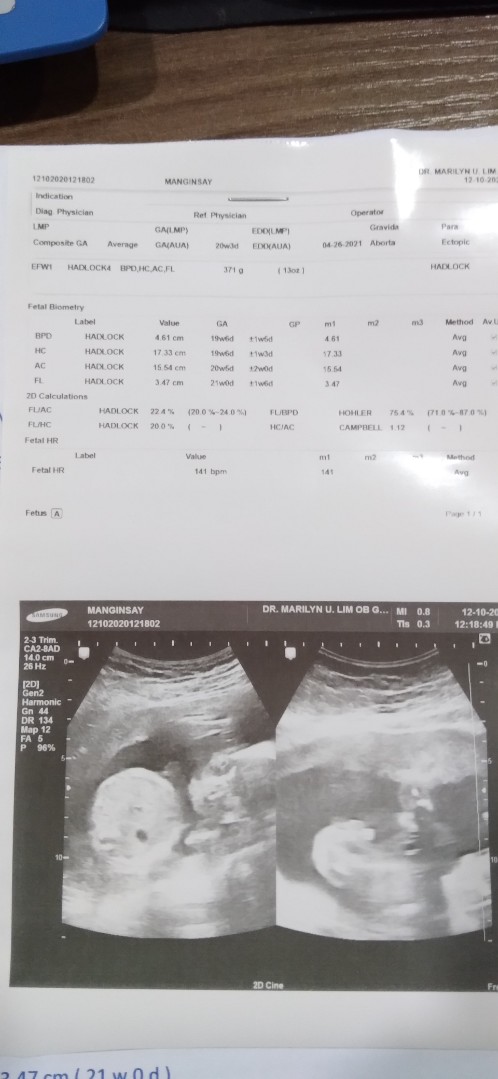

ngayon lang ako ngpa-ultrasound, right side, it's a boy